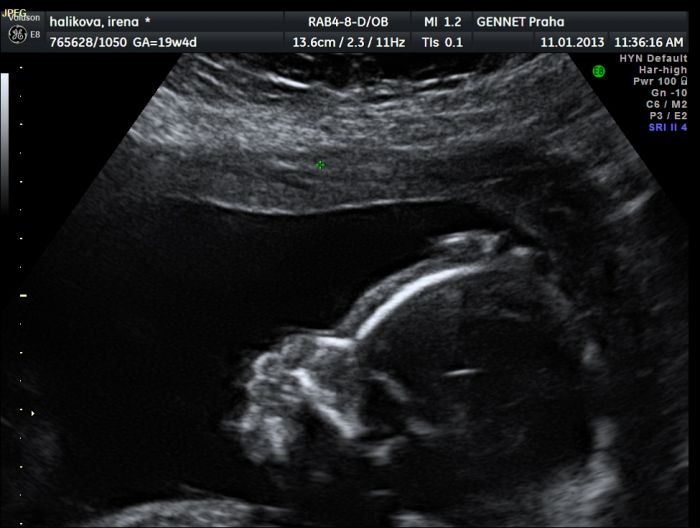

Ahoj holky, strašně dlouho jsem nenapsala žádný příspěvek, ale čtu vás pravidelně ;-). Jen pro připomenutí, jsem snažilka po dvou revizích, co nakonec otěhotněla po Pregnylu :-). Teď jsem 22tt, od prosince mám pohyby a všechny testy v pořádku. Pokusím se připojit fotečku, mimi se tam hezky drží za hlavičku, asi se nechtělo fotit :-). Pohlaví jsme si říct nedali, chceme překvapení :-).